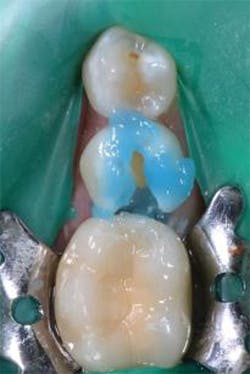

Figure 12: Final preparations on teeth Nos. 4 and 5. The Palodent Plus Sectional Matrix System has been used to isolate the MOD prep on tooth No. 4 and MO prep on tooth No. 5. The Palodent Plus Sectional Matrix System can be configured to restore multiple surfaces and multiple teeth in the same quadrant.